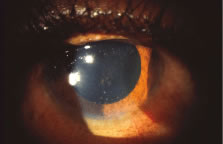

The ARN patient typically presents with progressive visual blurring in one or both eyes occurring over several weeks. These patients often are initially treated with corticosteroids, antitoxoplasmosis drugs, and other medications before arriving at the correct diagnosis. Examination reveals a prominent anterior uveitis that may be granulomatous or nongranulomatous (Fig. 1). Inflammatory signs may be prominent and cause severe pain (Fig. 2). The uveitis may be diffuse and so severe that it causes proptosis. These signs, and the diffuse vitreitis that makes the view of the retina difficult, may contribute to the high degree of delayed and/or misdiagnosis that occurs in the early stages of the disease. Significant vitreous cellular infiltration is seen in the presence of retinitis that is manifest by opacification of the retina, often most prominently in the periphery. Posterior pole involvement may include retinitis, as well as inflammation of the optic nerve head. Optic neuropathy might be the first sign of ARN with subsequent development of other retinal manifestations.8 Ultrasonography and computed tomography (CT) might be helpful in cases of ARN associated with optic nerve edema revealing enlargement of the optic nerve sheath.9 Even in ARN patients who are not immunocompromised and who have no clinical evidence of encephalitis, magnetic resonance imaging of selected cases has shown lesions of the lateral geniculate, optic tracts, and chiasma, which suggests that the virus spreads through the central nervous system (CNS) by axoplasmic transport from the retinal ganglion cells.10 A secondary retinal vasculitis is common, often accompanied by a mild number of retinal hemorrhages. Days to weeks after onset of the infection, the discrete peripheral lesions typically coalesce into a white or yellow ring of infected retina, and the associated vasculature is obliterated (Fig. 3). Necrotic retina desquamates into the vitreous resulting in vitreous sheets.3,6 Eventually, most untreated eyes can be expected to develop retinal detachment resulting from development of multiple full-thickness retinal breaks accompanied by traction or exudation.11 Giant retinal pigment epithelial tears have also been reported.12